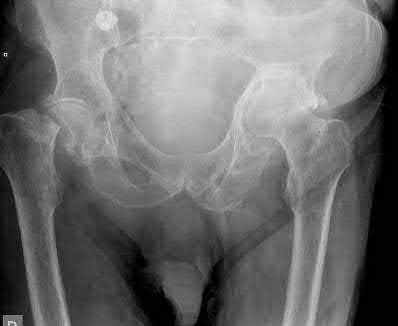

A 12-year-old obese boy presents with vague left thigh and knee pain. He is diagnosed with a Slipped Capital Femoral Epiphysis (SCFE) as seen in similar clinical scenarios.

During percutaneous in-situ fixation, unrecognized penetration of the guide wire into the hip joint occurs. What is the most likely specific complication resulting from this technical error?

Chondrolysis is a severe complication of SCFE characterized by rapid destruction of the articular cartilage. While it can occur idiopathically, its most established iatrogenic cause is unrecognized intra-articular hardware penetration. The 'approach-withdraw' fluoroscopic technique is required during pinning to assure pins are entirely intraosseous. Avascular necrosis (AVN) is usually due to damage to the epiphyseal blood supply (retinacular vessels) secondary to the initial displacement, forceful closed reduction, or posterosuperior pin placement.